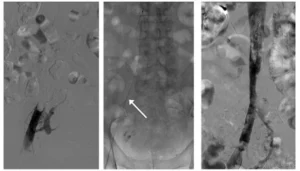

Il filtro cavale è rimovibile e può essere rimosso in seguito, quando il rischio di migrazione dei trombi è stato risolto (ad esempio, una volta che la trombosi venosa profonda è guarita). La rimozione avviene sempre sotto guida radiologica, con un approccio minimamente invasivo.

Rimozione di filtro cavale con apposito sistema (freccia bianca)